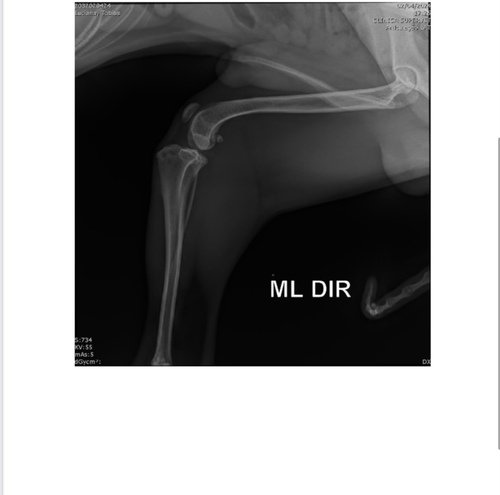

Gente esse meu cachorrinho tem 10 meses está com um problema muito sério, ele esta com desvio medial de patelas esquerda e direita em relação ao respectivo sulco troclear, sugerindo com severa luxação de patelas.

Segue o raio X